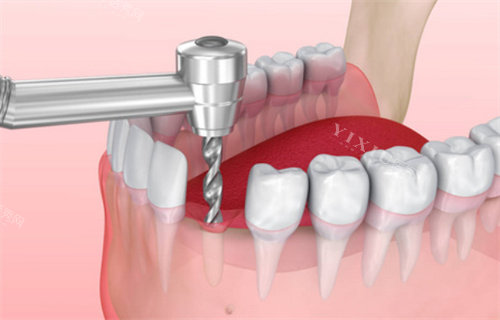

种植牙:采用韩国登腾、德国ICX等出名种植系统,支持即刻种植、小创口种植技术;